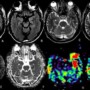

An elderly male, known diabetic with one episode of seizure. What is the diagnosis?

FLAIR shows cortical hyperintense signal in left temporal lobe. Subcortical hypointense signals are seen in T2-w images. No diffusion restriction is seen. ASL shows hyperperfusion.

Final diagnosis – Seizures associated with non- ketotic hyperglycaemia (NKH)

- Cortical hyperintense signal changes with/without diffusion restriction and reversible sub-cortical hypointense signal changes are the MR imaging features.

- ASL hyperperfusion secondary to hyperglycemia-induced increased blood-brain barrier permeability and may remain persist for longer duration.